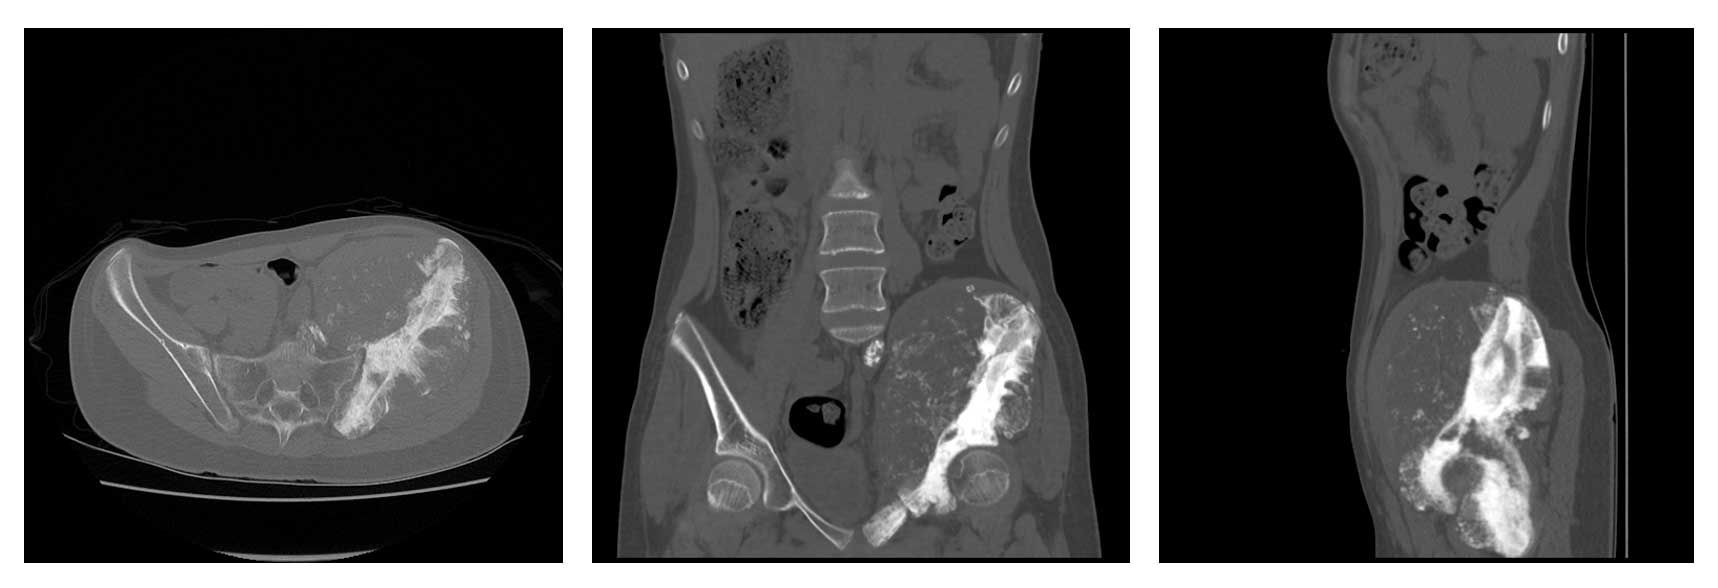

Ameliyat Öncesi: Tomografide lomber 5. vertebra, sakrum ve iliak kanatın tamamını tutan kemikte harabiyete neden olup yumuşak dokuya uzanan büyük tümör dokusu görülmekte.